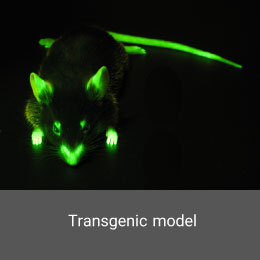

- Create and induce a variety of animal models